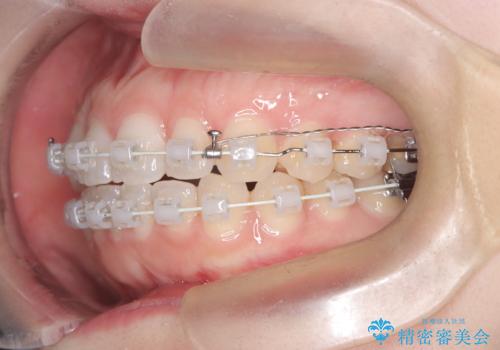

- 右上の八重歯と歯並びのデコボコを気にされて来院されました。精密な検査の結果、歯列のスペースがわずかに不足していることが判明。患者様の「抜歯を避けたい」というご希望を最大限に尊重し、アンカースクリュー(TAD)を用いて奥歯(臼歯部)全体を後方へ移動させることで、八重歯が並ぶスペースを確保する治療計画を立案しました。装置にはワイヤー矯正を使用し、確実で効率的な歯の移動を目指します。

今回のワイヤー矯正治療では、抜歯せずに歯を並べるスペースを作るため、特殊な小さなインプラントであるアンカースクリュー(TAD)を一時的に使用しました。このアンカースクリューを固定源として、奥歯(臼歯部)全体を後方へ遠心移動させました。従来の矯正では難しかったこの奥歯の移動を確実に行うことで、前歯の八重歯を適切な位置に並べるスペースを確保。治療の結果、抜歯することなく右上の八重歯と叢生が解消され、機能的にも審美的にも整った美しい歯並びを獲得していただけました。